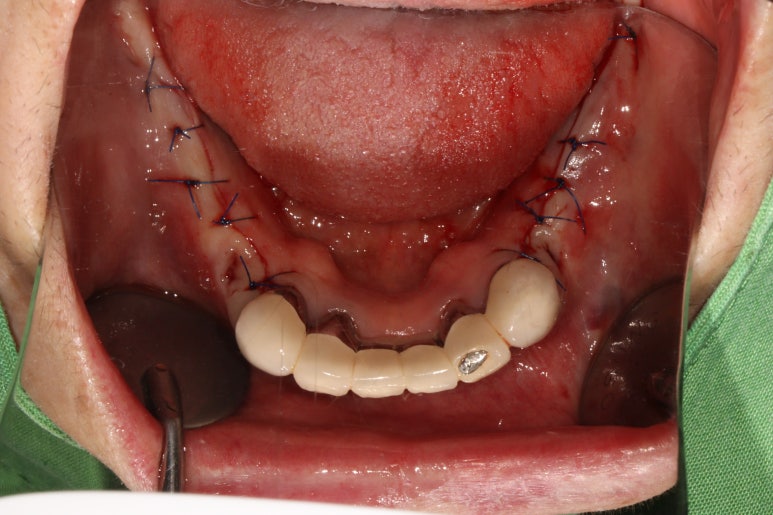

수술이 끝나고 깔끔하고 예쁘게 꿰매드렸습니다.

임플란트 개수 자체는 많지만, 네비게이션 임플란트 수술 시스템을 이용하여 빠르고 덜 침습적인 수술을 하게 됨으로써 수술 후 통증을 최소화 시킬 수 있습니다.

수술 후 촬영한 치과용 파노라마 사진에서, 정~말 깔끔하고 예쁘게 식립된 임플란트를 보실 수 있습니다.

아래턱뼈 내부에는 하치조신경이라는 감각신경이 주행하고 있는데요, 네비게이션 임플란트를 통해 수술 후 감각마비 없이 깔끔하게 마무리 되었습니다.